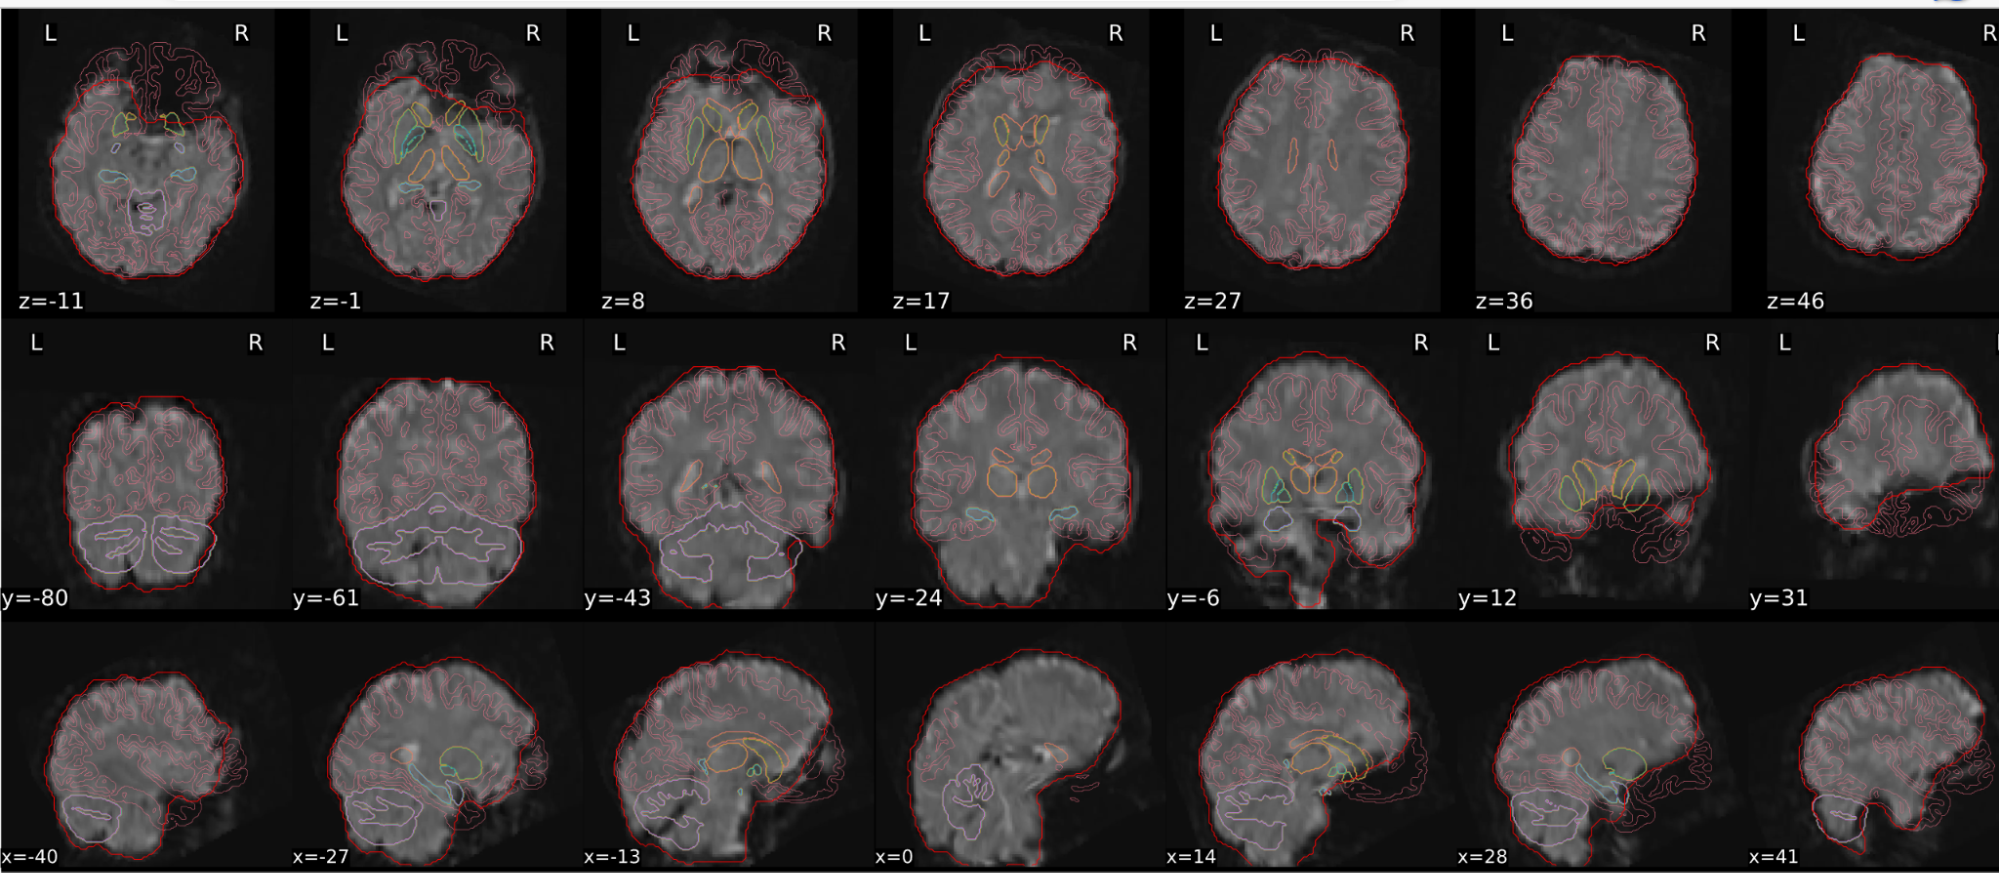

EPI spatial normalisation

This QC step shows the registration of the EPI image to MNI space.

Example of a good subject

- If the registration performed well, you should see an overlap (i.e., correspondence of structures) between the MNI template and the EPI registered to the MNI space.

- If parts of the brain are missing due to the scanner field of view, this is fine. For example, the cerebellum may be cut off for a participant with a large head.

Example of a bad subject

- In case of poor registration, you should see a misalignment of the EPI and the MNI template

Summary

| good | bad |

|---|---|

| Overlap (i.e. match of structures) between the MNI template and the EPI registered in the MNI space | Misalignment of the EPI and the MNI template |

| If parts of the brain are missing because the field of view of the scanner is limited, the EPI spatial normalisation does not have to be excluded e.g. cerebellum cut off in person with large head |

If parts of the brain are missing because the field of view of the scanner is limited, the EPI spatial normalisation does not have to be excluded (e.g. cerebellum cut off in person with large head)